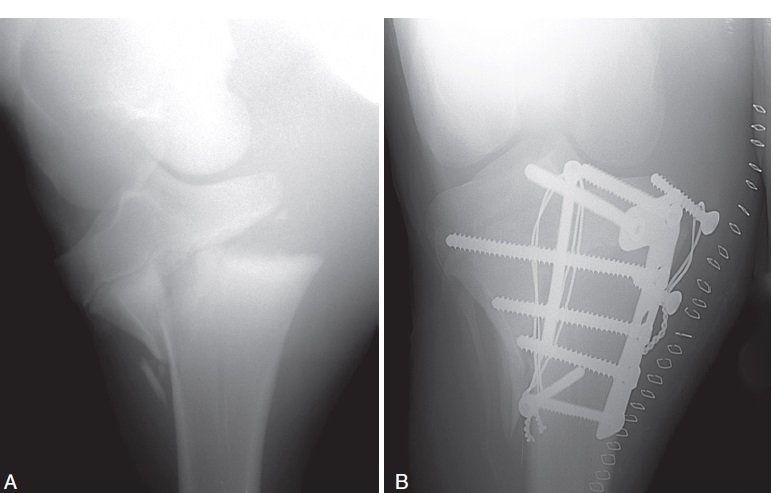

Figure 100-7. (A) A caudocranial intraoperative fluoroscopic view of a proximal tibial physeal fracture repaired with a four-hole T-plate. This fracture was more severe than a routine proximal tibial physeal fracture and required a more involved fixation. The metaphyseal component is comminuted and extends more than half the width of the bone. In addition, there is only one screw that is anchored in healthy bone distal to the comminuted fracture. This fracture probably required two implants and more distal fixation to resist the biomechanical instability the comminution created. (B) The caudocranial follow-up radiograph taken the next day because the foal was non–weight bearing on the limb. A catastrophic bone failure occurred during the night. The fracture initiated at the distal end of the original fracture and spiraled distally, leading to catastrophic failure of the bone. The owner did not want to proceed with treatment and the foal was humanely destroyed.